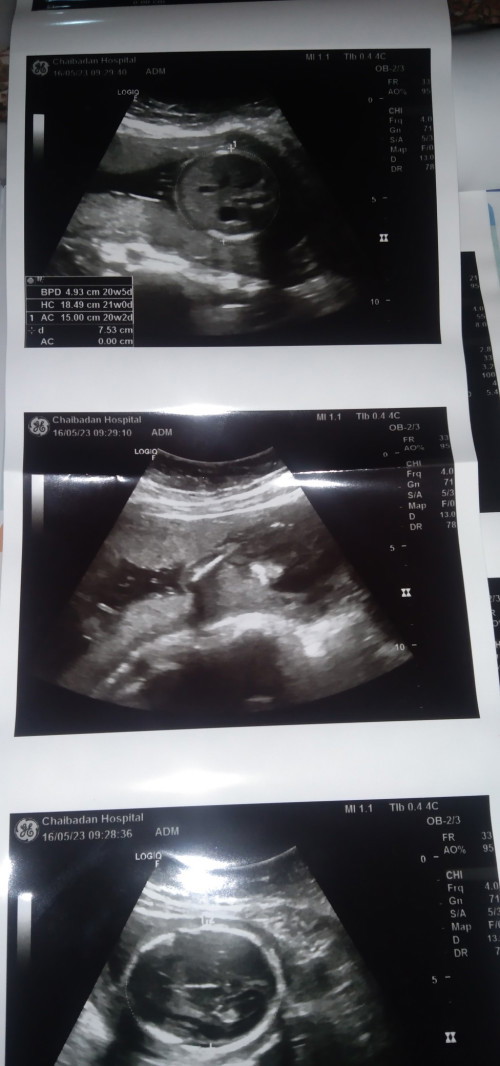

8w ค่าาา❤️❤️